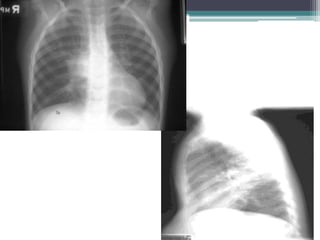

Cervicothoracic sign

Which compartment do you think this mass is in?

See sharp

margin

above clavicle

โ€ข Answer: Mass is in posterior mediastinum. We

know because it remains sharply outlined in apex of

thorax, indicating that it is surrounded by lung.

โ€ข This particular example is a ganglioneuroma

โ€ข Answer: Mass lies in anterior mediastinum. We

know this because it disappears at the level of the

clavicle where it extends into the neck.

โ€ข This particular example is Non-Hodgkins lymphoma